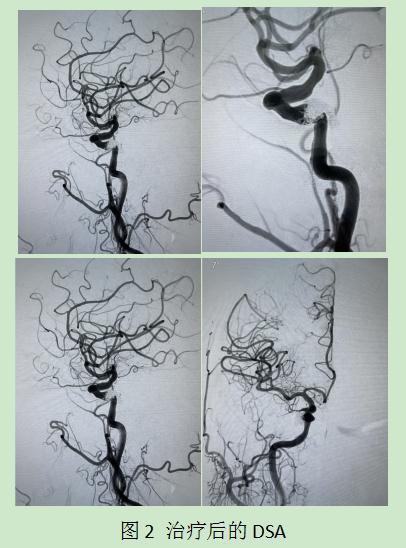

由于病例少见,治疗团队在黄涛主任和张迎光副主任医师主持下进行讨论,决定使用神经介入微创手术治疗该患者。手术由陈发军医师主刀,采用“弹簧圈+ONYX胶栓塞”技术,术中完全栓塞瘘口,手术顺利。术后,患者眼球红肿明显减轻,视力也开始恢复。